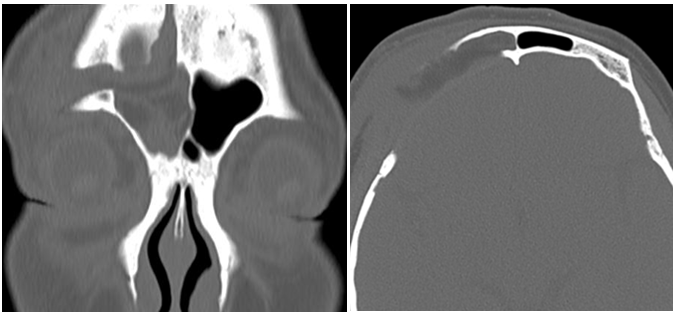

病人女42岁鞍结节脑膜瘤术后2年,眶周红肿2月,刀口不愈合,有两处破溃,流脓,额中部隆起,当地换药后不见效。

神经外科开颅术后刀口不愈合,必有原因,一是附近有副鼻窦或乳突腔,副鼻窦内常有骨蜡,导致额窦腔引流不畅,轻者额中部无痛性隆起,严重者可在薄弱处破溃。二是过多人工材料的使用,引流不畅时细菌在人工材料上定置,导致感染的发生。